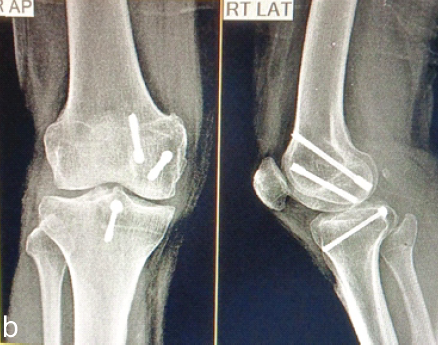

Restoring Sagittal Alignment: Anterior Open-Wedge Flexion Valgus Osteotomy for Post-Traumatic Genu Recurvatum with Reversed Posterior Tibial Slope – A Rare Case Report

Sunil Khemka , Ambrish Verma , Pritam Agrawal , Ram Khemka , Pradeep Patel

………………………………p.104-109